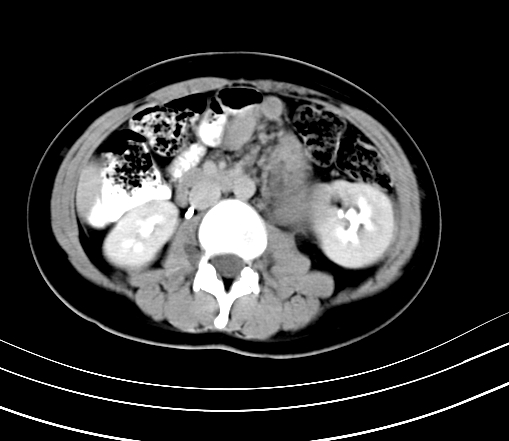

动脉期